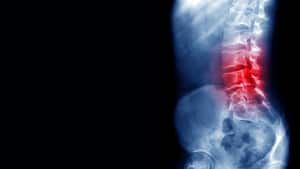

El dolor de espalda al despertar puede tener varias causas. Según la Asociación Estadounidense de Quiropráctica (ACA), una de las principales razones es la mala alineación de la columna vertebral durante el sueño. Dormir en una posición que no brinda un soporte adecuado a la espalda puede generar tensión en los músculos y las articulaciones, resultando en rigidez y dolor.

Para prevenir el dolor de espalda al despertar, es fundamental adoptar la postura de sueño correcta. La Fundación Nacional del Sueño de Estados Unidos (NSF) recomienda dormir de lado o boca arriba, ya que estas posiciones ofrecen un mejor soporte para la columna vertebral.

Por otro lado, la postura de dormir boca abajo debe evitarse, ya que puede generar una tensión excesiva en el cuello y la espalda baja. Esta posición puede provocar una hiperextensión de la columna cervical y comprimir las vértebras lumbares, causando dolor y rigidez.